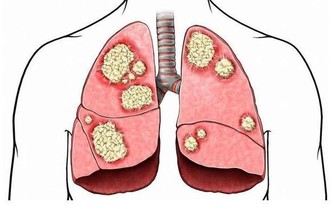

飢餓性酮症

醫學研究證明,如果人體長時間得不到足夠的外源性能量補充,一方面將導致體內脂肪和蛋白質過量分解,造成身體消瘦,長期營養不良,甚至會產生飢餓性酮症;